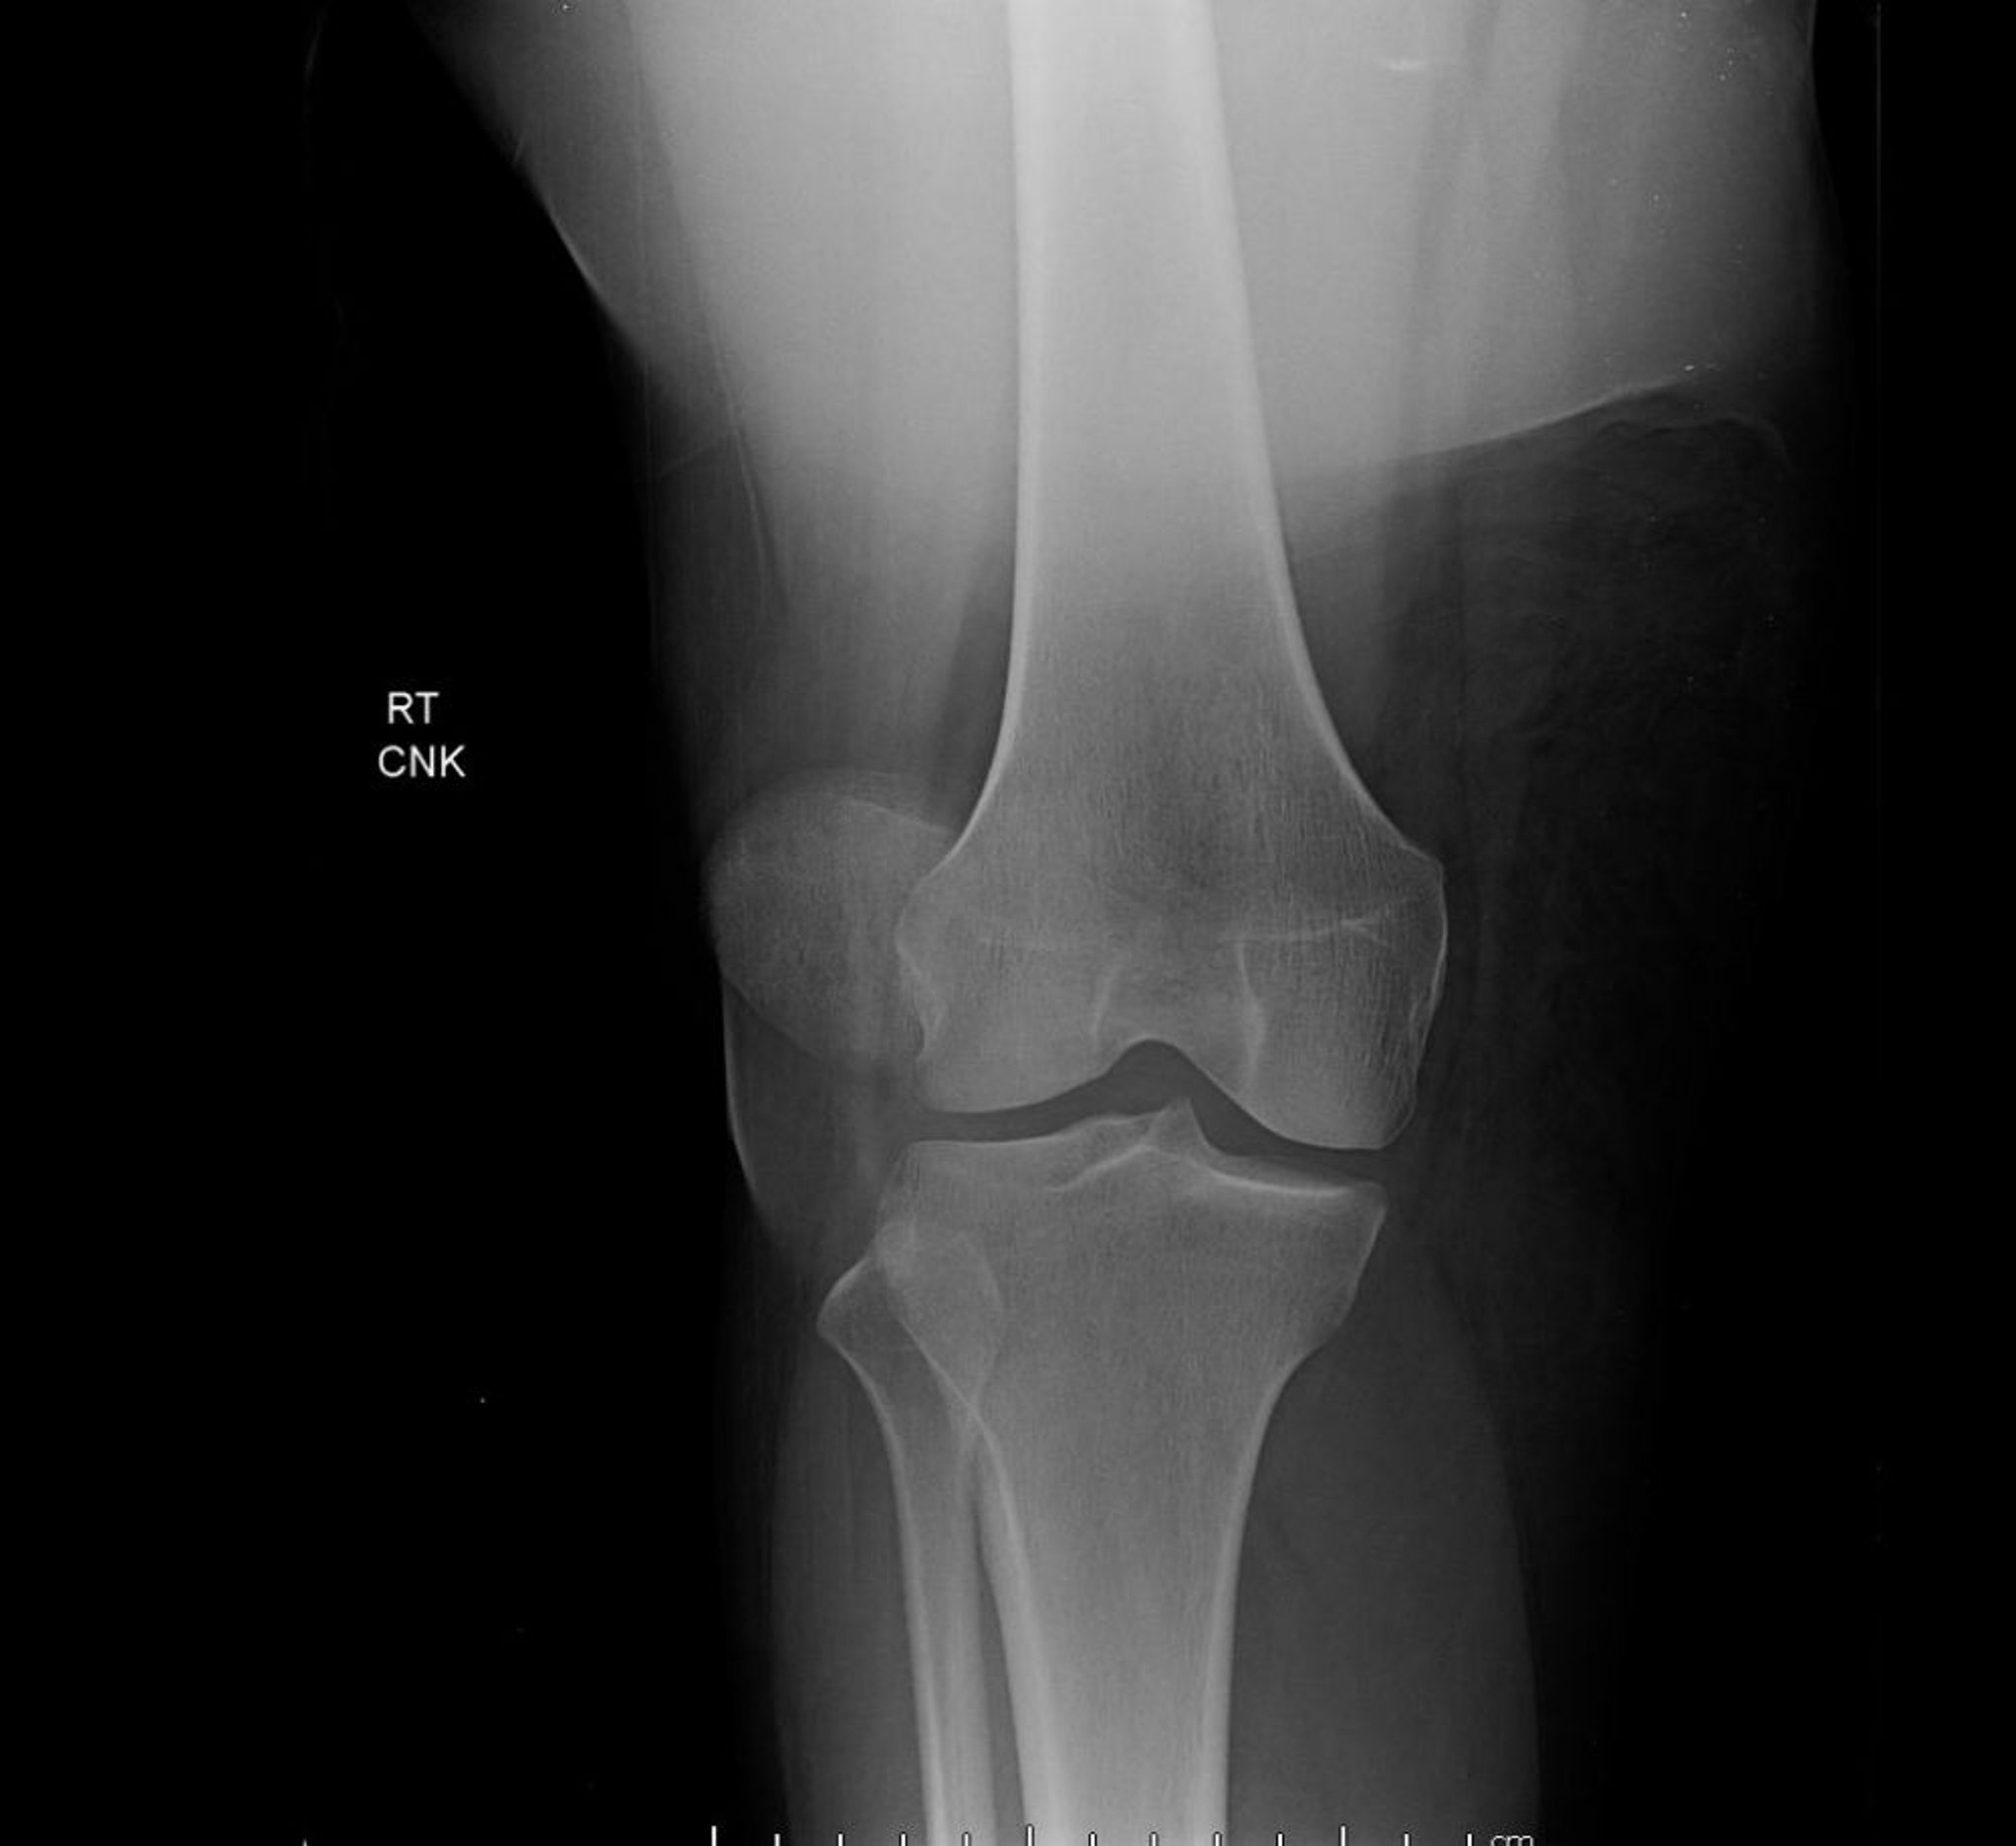

Diese anteroposteriore Ansicht des Knies zeigt eine Patellaluxation, die durch eine extreme seitliche Verschiebung der Patella außerhalb ihrer normalen Lage zwischen den Femurkondylen gekennzeichnet ist.

Image courtesy of Danielle Campagne, MD.